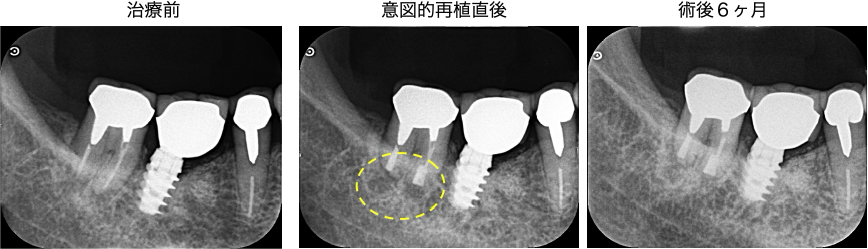

術前-術後の比較

術前と術後のレントゲン・CT画像を比較すると、根の先の黒い影(根尖部の透過像)の縮小傾向を認め、経過良好といえます。

D根(遠心根)のみわずかに黒い影は残っていますが、治る方向へ進んでおり、時間経過とともに完全に治癒すると考えられます。

症状もないため、このまま継続的に経過観察を続ける予定です。